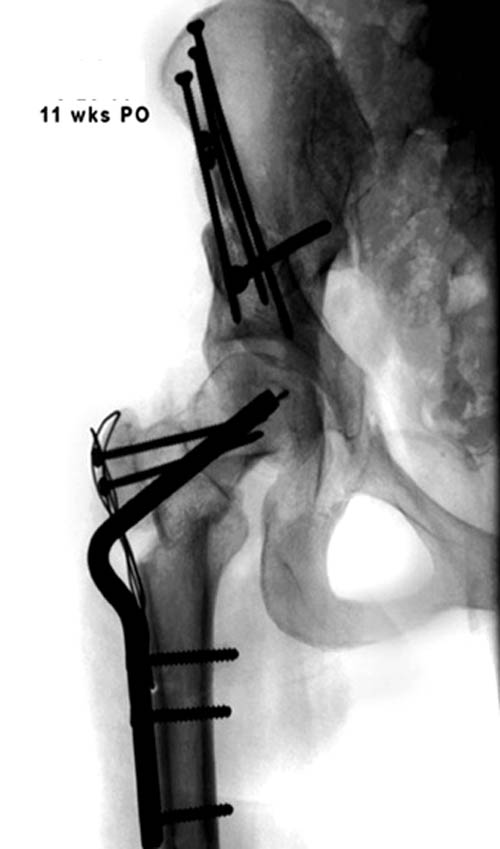

Здесь комбинированная патология тазобедреннего сустава, связанная с высокостоящим вертелом и отсутствием (ротирована?) шейкой. А на стороне вертлужной впадины диспластический сустав. Обычно высоко расположенный вертел приводит к уменьшению силы мышц абдукторов, но отстутствие шейки привело к вертикальному расположению  сил в суставе. Боли появляются из-за вертикального давления, а неровные контуры головки приводят к ограничению движений в суставе. Такое состояние быстро изнашивает сустав, и больные в молодом возрасте заканчивают тотальным протезированием.

Протезировать может любой специалист по артропластике, но все таки молодой возраст, не очень приятная перспектива. Желательно сохранить собственный сустав и иногда  укорочение конечности можно устранить за счет удлинения шейки, а в дальнейшем Периацетабулярная Остеотомия. Но, еще раз повторяю, иногда!

Представленный случай имеет схожесть....,  и последний снимок после 2 х лет.